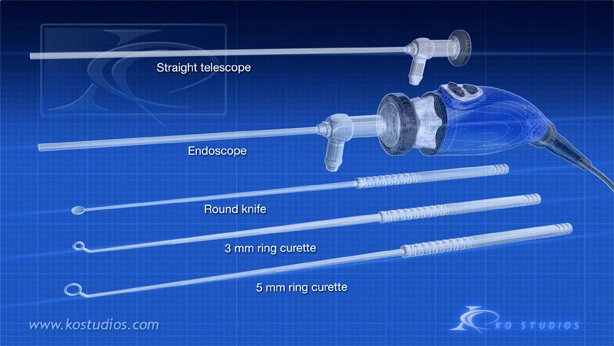

Endoscopic Pituitary Surgery-Nasal Approach

“A pituitary tumor is an abnormal growth of cells within or around the pituitary gland. Most pituitary tumors are non-cancerous growths called adenomas, which do not spread to other parts of the body. However, pituitary adenomas can cause the pituitary gland to produce too many or too few hormones, causing a variety of symptoms.”

This animations depicts tumor removal via the nasal approach.

Copyright©2021: BNI, Authors: KO Studios,

Narration: Dr. Andrew Little

https://www.barrowneuro.org/condition/pituitary-tumors/